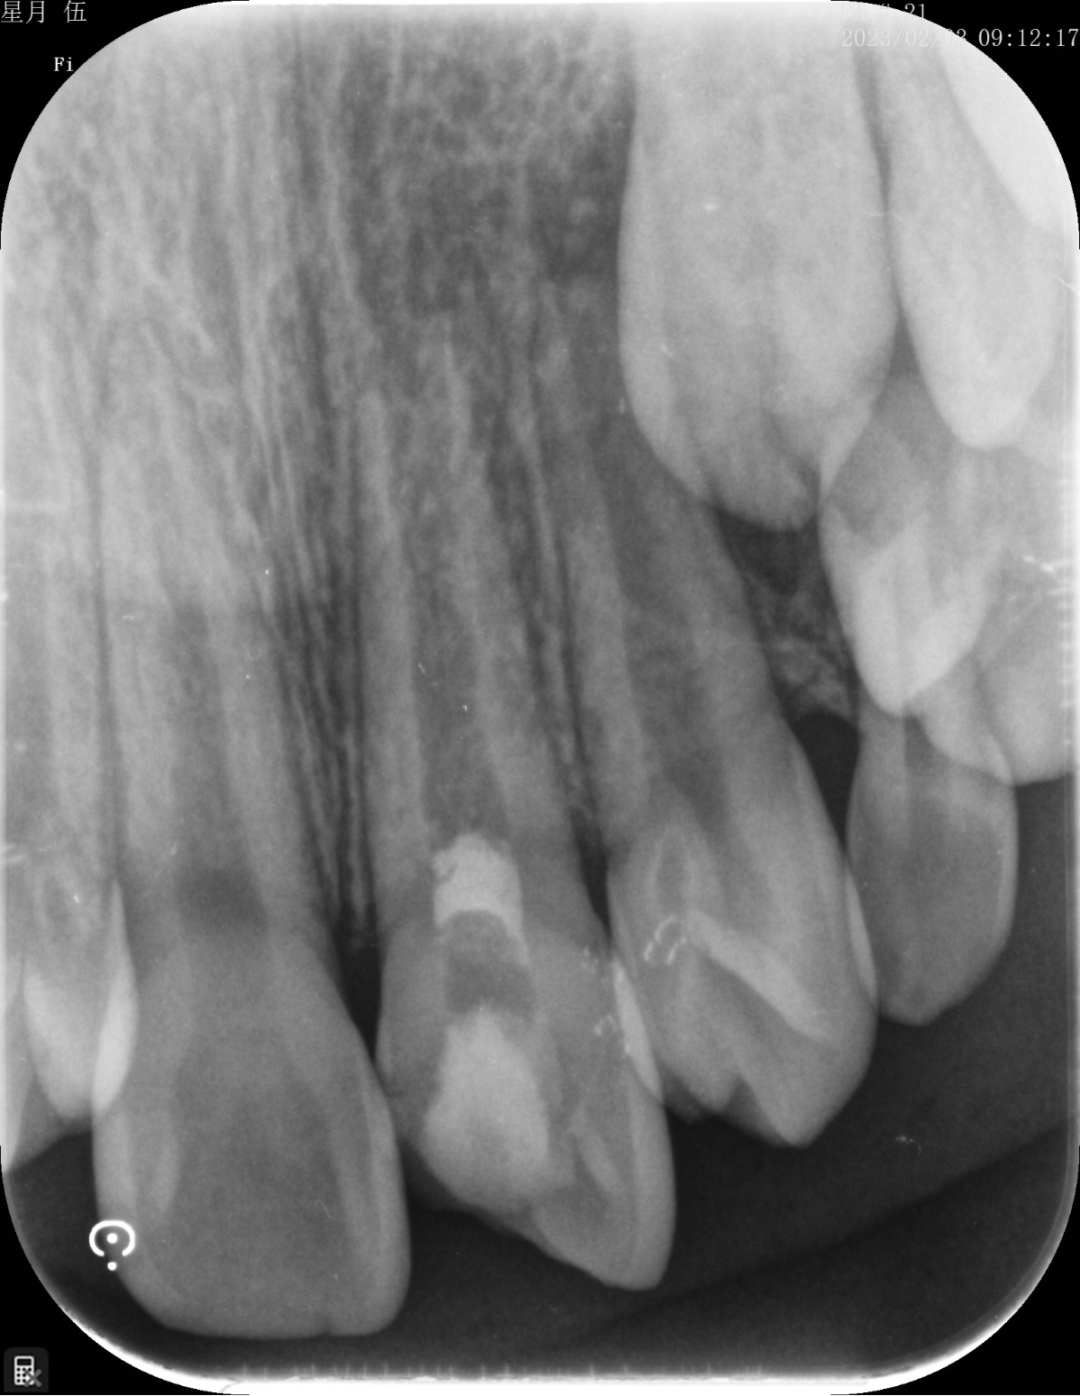

“起死回生”技术

“牙髓再生”技术是我科室率先在资阳市开展的生物组织学工程技术,利用自体血液促进仿牙髓组织再次发育,促进年轻恒牙牙根继续发育直至发育完成。相比传统技术,可以有效增加牙根的长度,粗度。

根尖炎症导致牙根停止发育

经过牙髓再生技术后,6个月后,根尖炎症消失,牙根长度增加,牙根的厚度增加